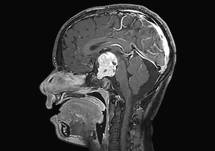

So typically, when patients have a tumor in an eloquent area, they usually present typically acutely. They can present to the emergency room, though they’re also sometimes seen as an outpatient, but if they do present to the emergency room, they would first have a head CT, which would likely show the mass. You know, that would be followed up with an MRI of the brain, with and without the contrast dye that would better demonstrate the mass, the structural location, and the characteristics of the mass, to give us an idea of what type of tumor it might be. And then, beyond there, there’s more testing that can be done to give us a better indication of how involved that mass is with an eloquent area, and Dr. Quinones, if you want to speak more in that regard, in terms of some of the preoperative evaluation that’s done to diagnose this.

Well, thank you Dr. Sherman. Indeed, they should do a functional MRI, of course. We have our multi-disciplinary team of neuropsychologists that help us understand how this potential tumor is having an effect on those eloquent and subtle functions that Dr. Sherman was alluding to. So we do not only functional, in regards to language, understanding of language, production of language, vision, memory, but also we look at the deep white matter connections that allow those areas of the brain to function as a unit. So, in essence, we try to understand, “How is this tumor affecting the quality of life of our patient, in addition to the language or the motor function?” And we are beginning to understand how will we go into the operating room to disconnect those areas, take a tumor out, and ideally leave the patient intact.